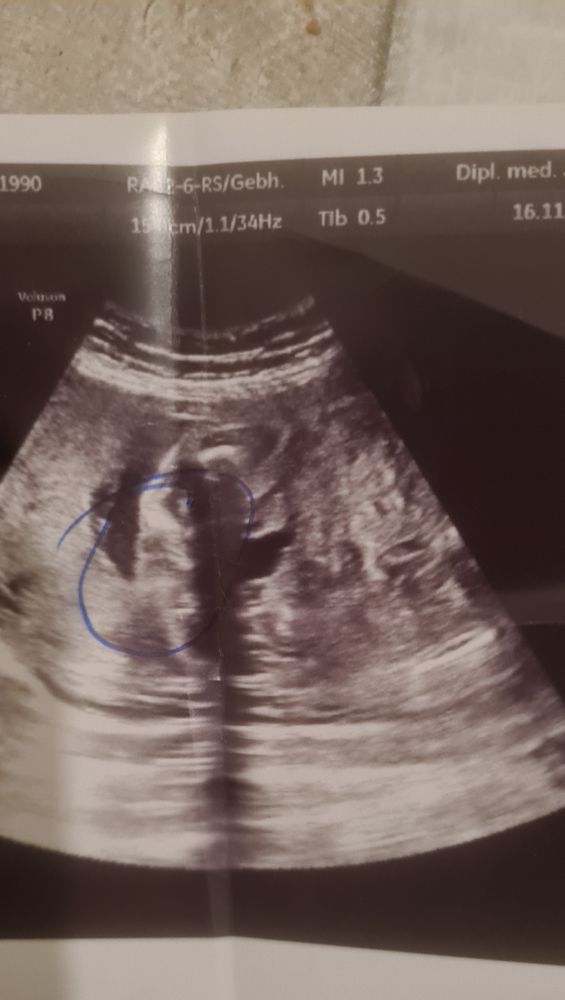

Вообще ниче не понятно если честно

АленаФеликсовна, Там в кружок обведены типа половые губы, но мне кажется это машонка просто папка не видна..я предпологаю))

Angel, вчера была на узи 7мь месяцев у меня уже, врач не смогла определить из за сильной активности ребёнка...а фото узи которое я прикрепила это узи от 25 недель, на фото типа половые губы, но узист сказала похоже на девочку) вот я и думаю, если она говорит похожа на девочку значит это может быть и мальчик)

Катя Катерина, да, похоже на губки..но может быть и машонка...врач точно не говорит..сомневается..хотя предполагает девочку